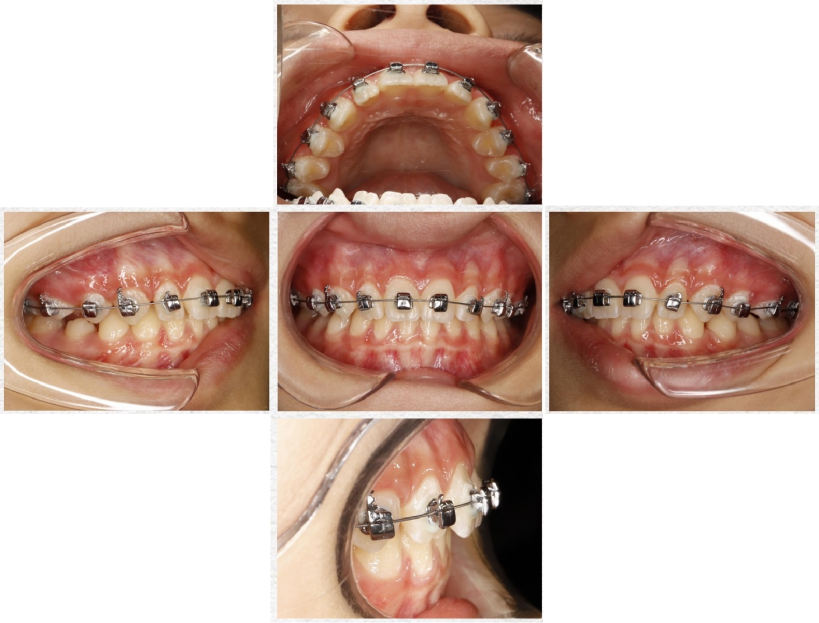

临床案例

注意:

1、如果尖牙牵引钩末端距离牙面过多,可以通过工具适度调整;

2、后牙如果咬合过紧,可以适度向龈方粘接托槽或适度调磨托槽。